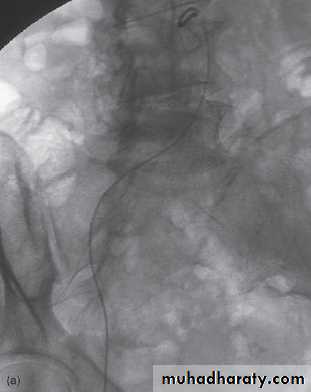

Digital subtraction angiography

Digital subtraction is a process whereby a computer removes unwanted information from a radiographic image. Digital subtraction is particularly useful for angiography, referred to as DSA.

Mask image contrast image subtracted image